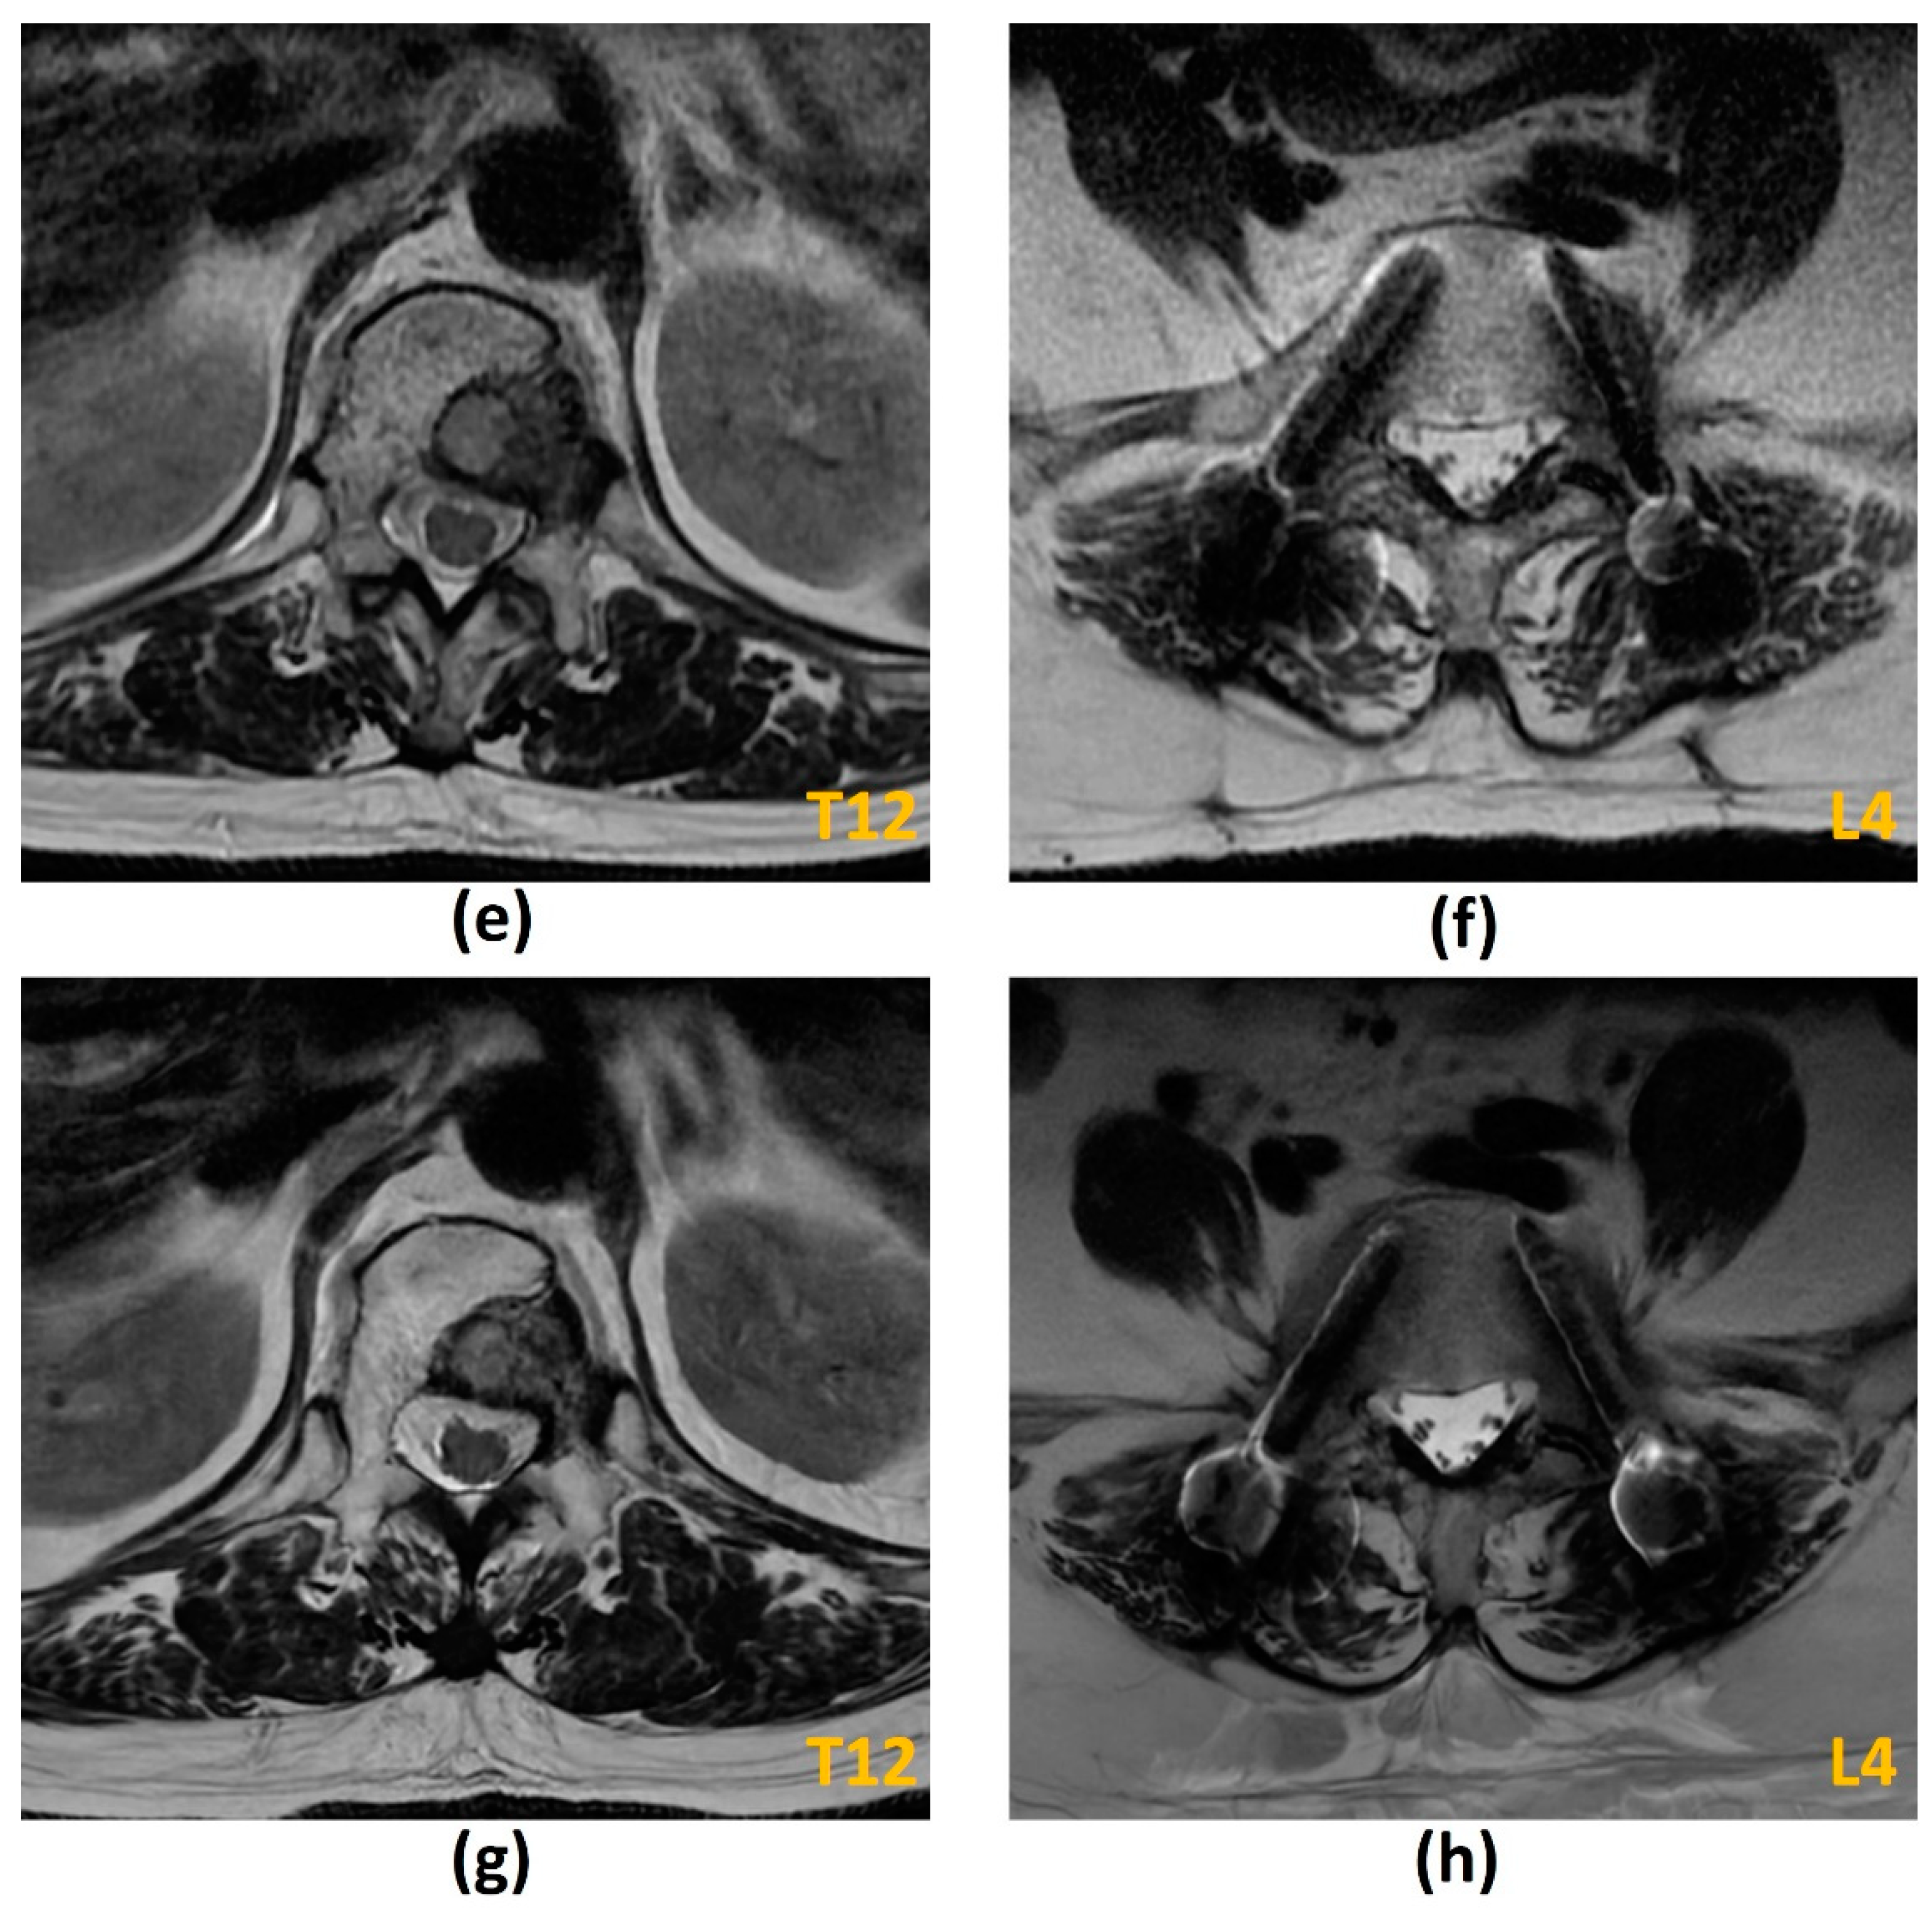

3.2. Magnetic Resonance Imaging (MRI)

3.2.1. Challenges of MRI: Metal-Related Artifacts